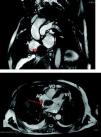

Hepatocarcinoma, una causa infrecuente de insuficiencia cardiaca derecha

Hepatocarcinoma, an uncommon cause of right-sided heart failure